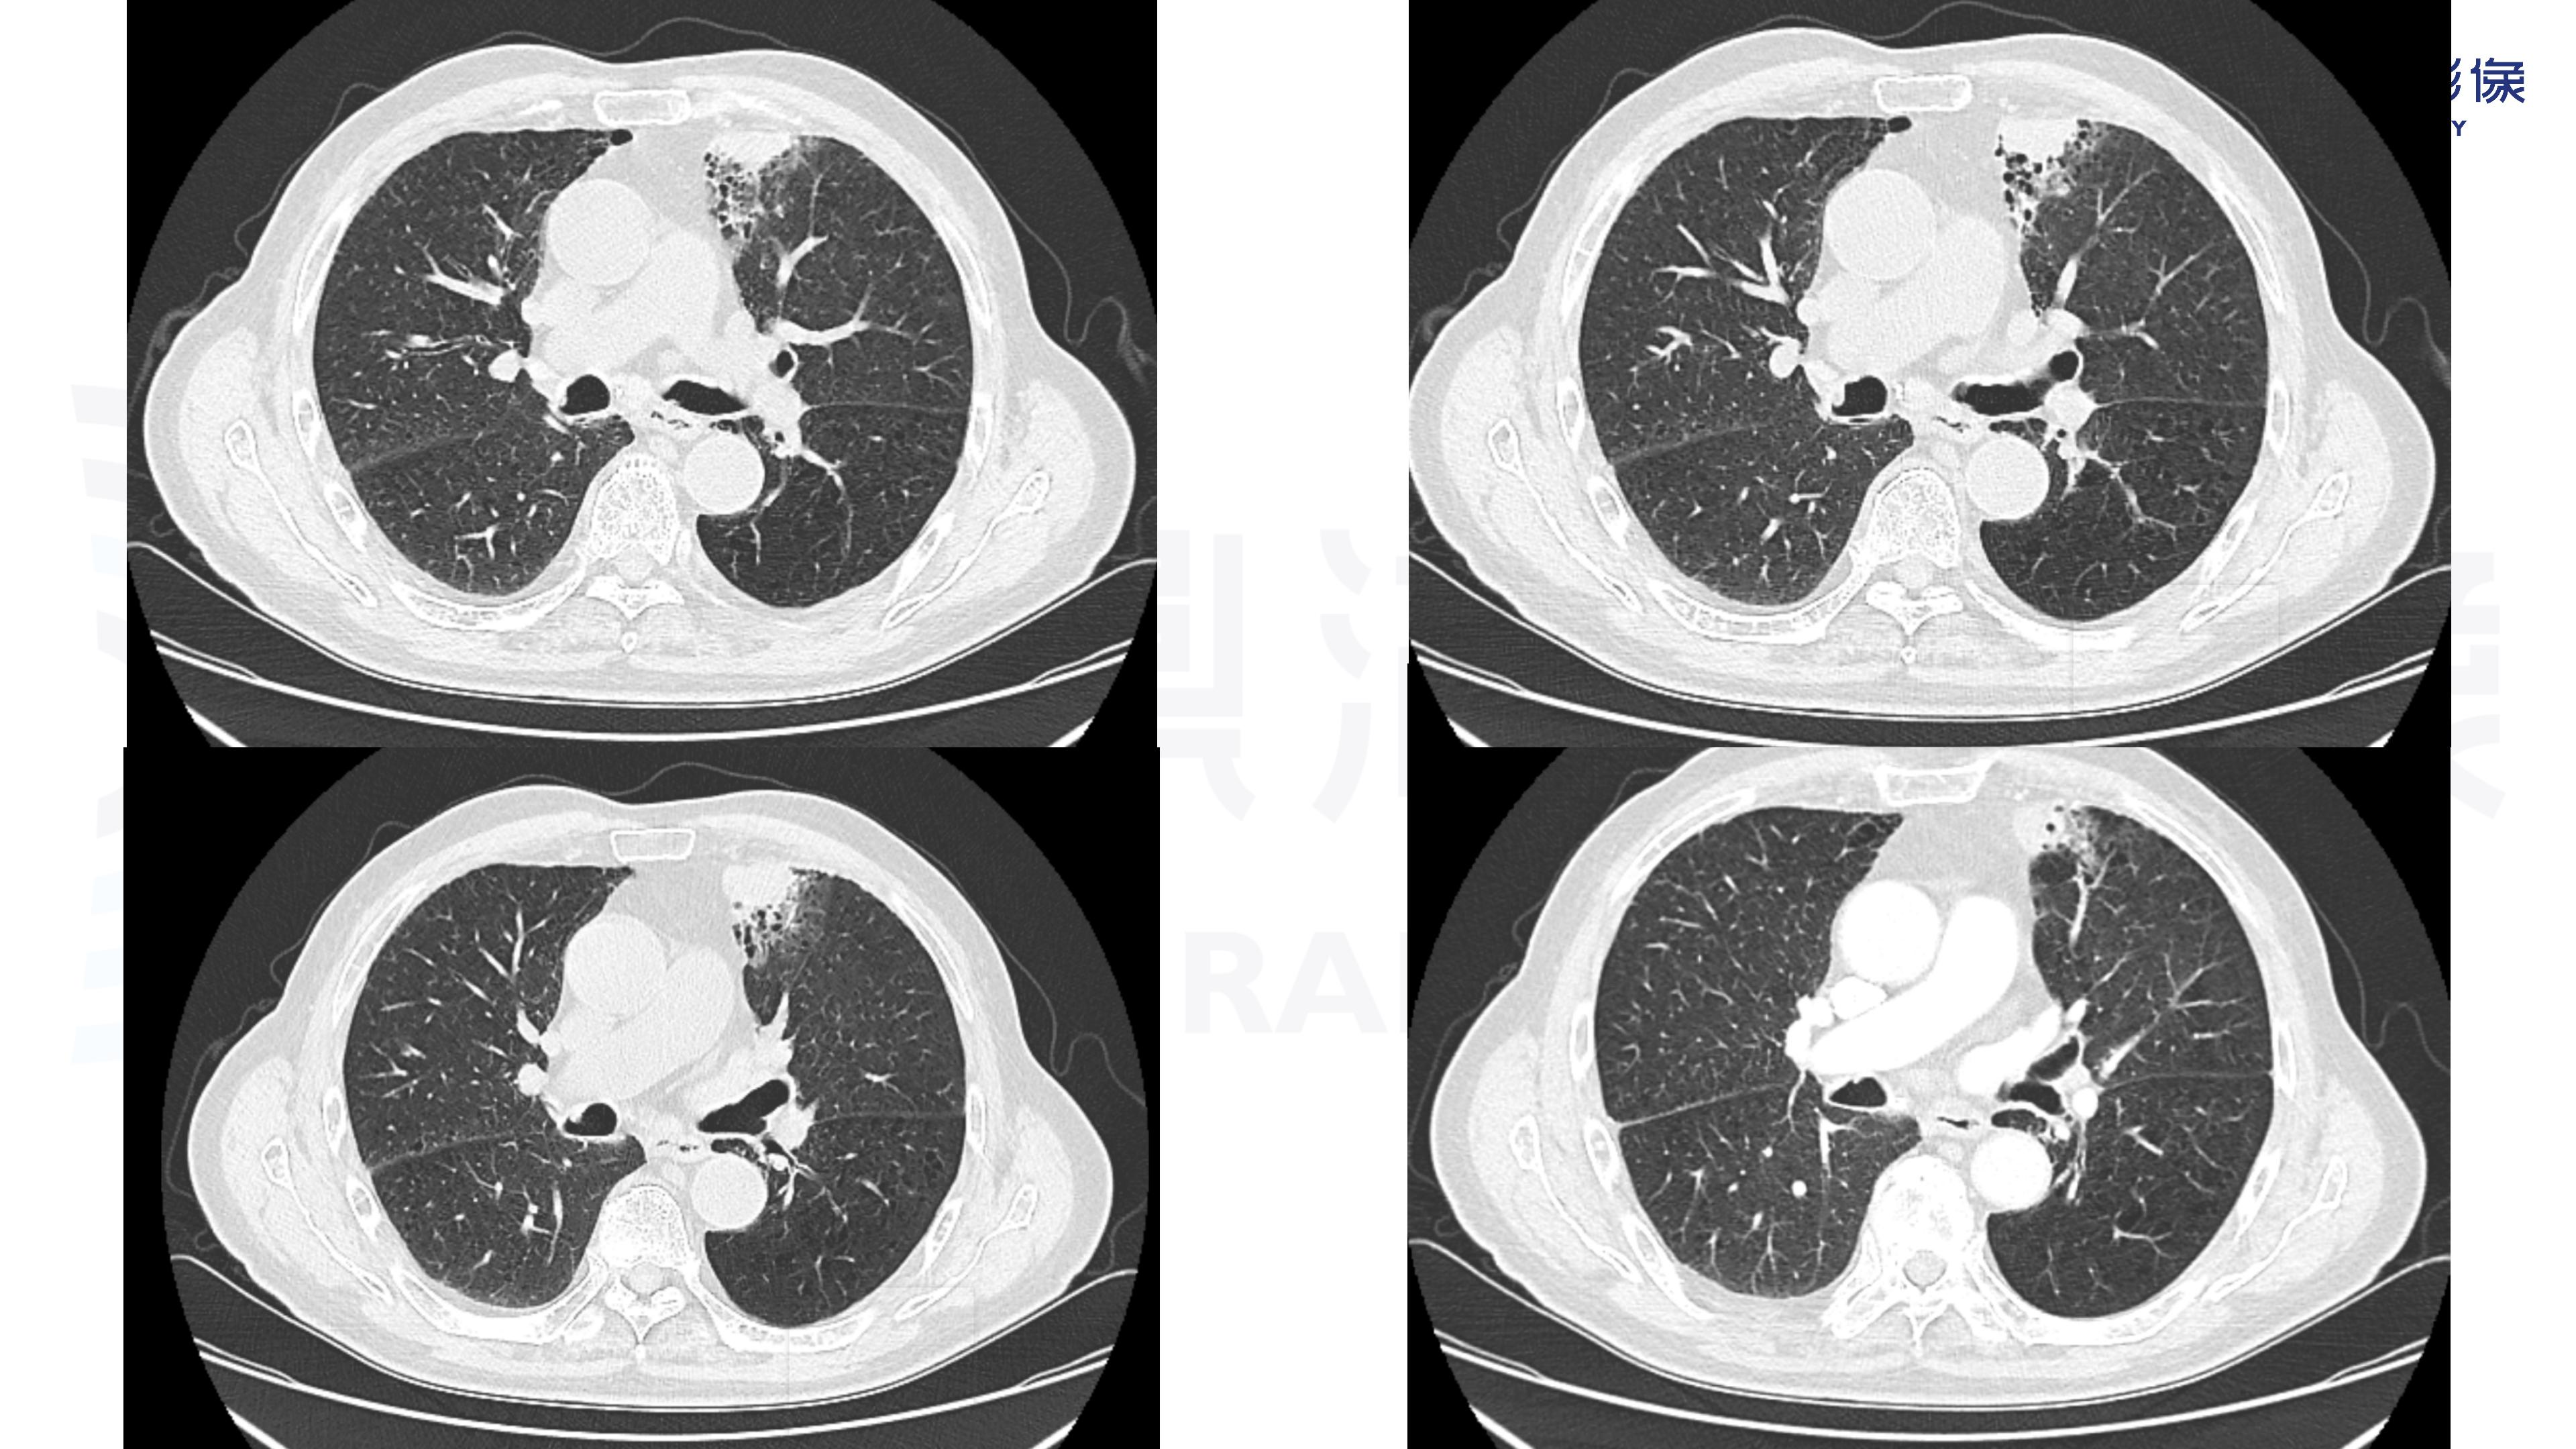

肺腺癌-鼎湖社群读片病例